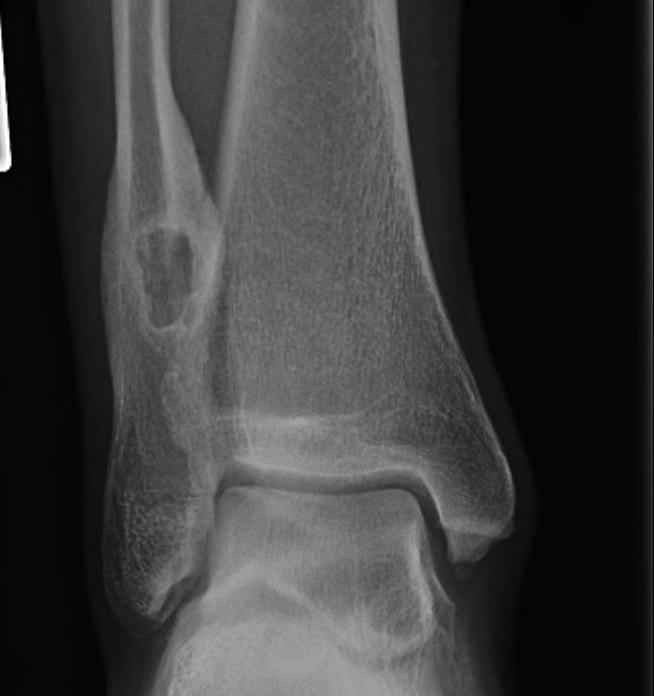

Talus

1. Head and neck

- medial approach between Tibialis anterior and Tibialis posterior

2. Body

- lateral Ollier's approach between Peroneus tertius and Peroneus brevis

Calcaneum

Direct lateral approach